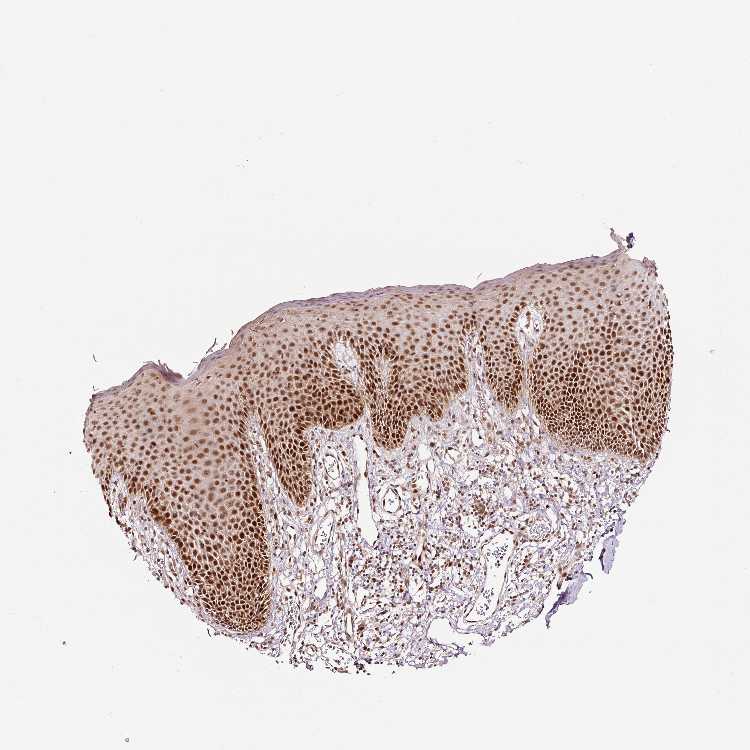

ADIPOSE TISSUE - Antibody stainingi

Antibody staining in the annotated cell types in the current human tissue is reported as not detected, low, medium, or high, based on conventional immunohistochemistry profiling in selected tissues. This score is based on the combination of the staining intensity and fraction of stained cells.

Each image is clickable and will lead to virtual microscopy that enables deeper exploration of all samples and also displays staining intensity scores, fraction scores and subcellular localization as well as patient and tissue information for each sample.

Antibody HPA049123Antibody HPA058507Antibody CAB004557

Adipocytes LowNot detectedMedium